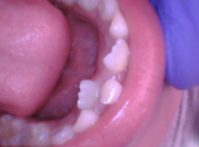

在八九十年代,几乎所有孩子到换牙期时,牙齿是自然松动、脱落。但看如今,大部分孩子到了换牙期,要么牙齿晃动但就是不自然脱落,要么没有任何晃动,更有甚者恒牙长出,乳牙仍旧坚固。还有很多人,牙齿疼就吃药、打针,疼完要么不再理会,要么就要求拔掉,宁愿不要这颗牙。